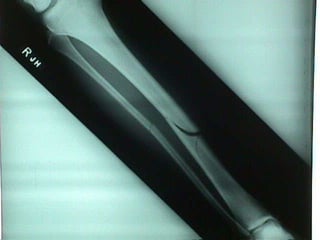

Tibia & Fibula

hematoma callus bony callus Repair of Fractures bone  remodeling

hematoma callus bonycallus Repair of Fractures bone remodeling